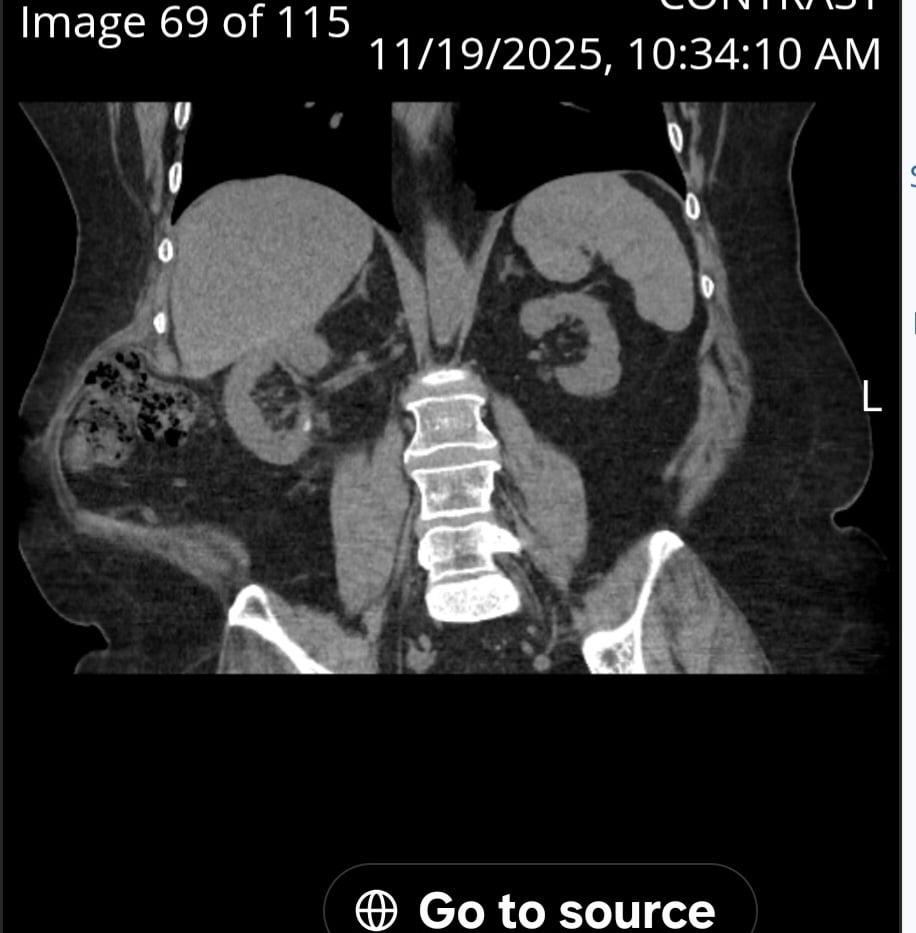

When I asked a specialist in hernias he said it would make it worse. And that mesh wouldn't fix it. I have read of them attaching mesh to rib and hip but then creates mobility issues. I don't see why I can't rebuild the muscles they cut. We're did they attach your mesh? Had your intestines move out of place? Did you ct ever look like this?

Yes, my organs were all out of place. Kidney, liver, colon, etc.